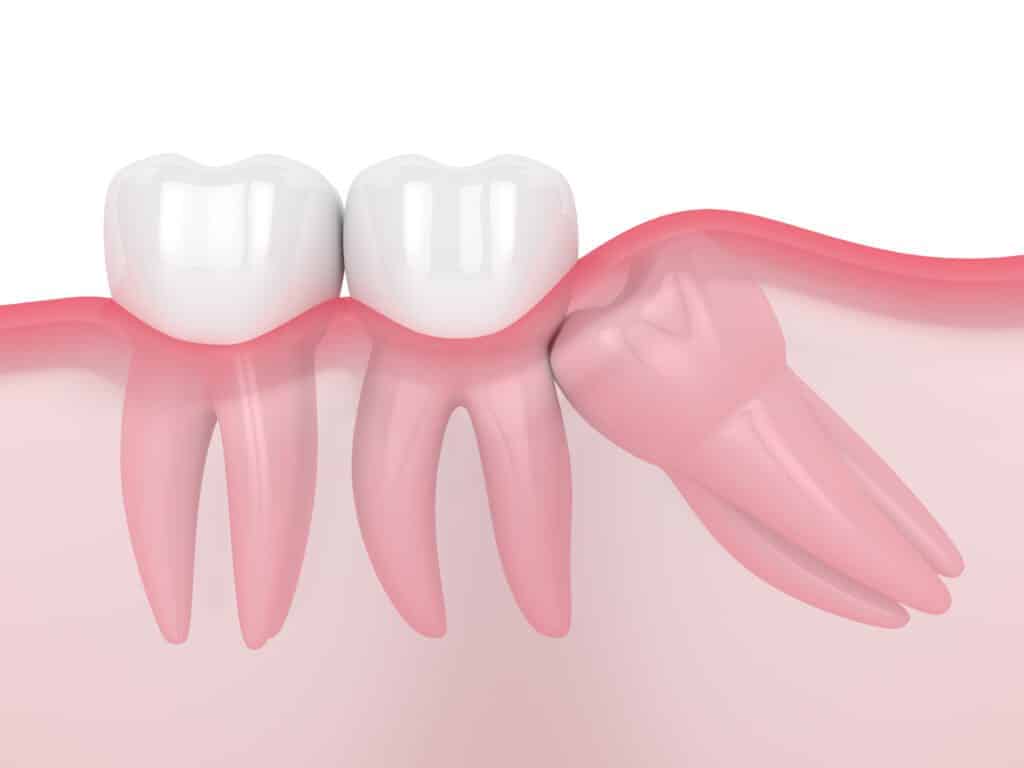

The dentist will determine based on the extent of the tooth loss and the bone recession whether or not implants are an effective solution to an individual’s tooth loss. Occasionally a sinus lift bone graft can provide additional bone to make the process possible. With enough jaw bone available, an implant’s titanium post is drilled into the jaw after all signs of the natural tooth root have been removed.

The specifics of installation surgery are dependent on where in the mouth the implant is added. Most single tooth implants are installed to replace a single back tooth. Premolars and molars are very often the first kind of teeth to be lost for two reasons: they experience the most wear because of their essential role in eating, and they are most susceptible to the effects of gum disease and decay.

Molars usually require a “two-phase” treatment sequence because they have at least two roots. When molars are replaced, any roots are first removed and then the bone is grafted (filled). A recovery of up to 12 weeks is common before the implant can be installed. Front teeth can also be replaced with dental implants. Because of the role of canine and incisor teeth in tearing food, installing an implant of the maximum size is good practice.